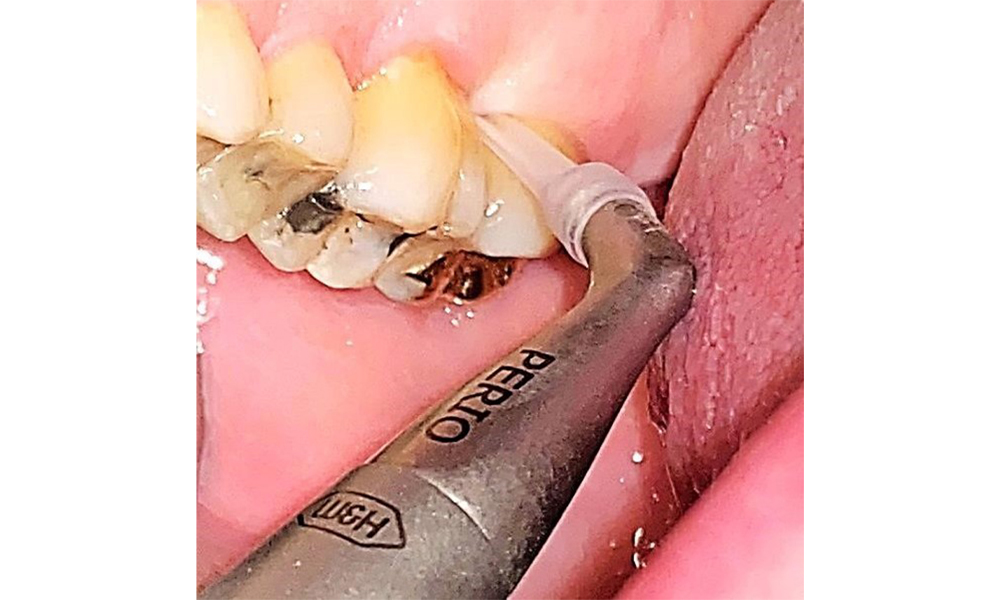

There are no limitations regarding the choice of instrumentation methods. Regular supragingival and subgingival instrumentation is essential to prevent disease progression due to the pre-existing periodontitis and high risk of recurrence. There are no limitations placed on the selection of instruments for mechanical biofilm removal from a general medical perspective, and removal should be performed as needed. Hard and mineralized plaque, such as calculus and concretions, should be removed using manual instruments or sonic/ultrasonic scalers (Fig. 9) (8, 9).

Use an ultrasonic tip to remove hard, mineralized plaque (Proxeo Ultra scaler with the Perio tip, W&H, shown here).

Fig. 9: Use an ultrasonic tip to remove hard, mineralized plaque (Proxeo Ultra scaler with the Perio tip, W&H, shown here). © Dr R. Krapf